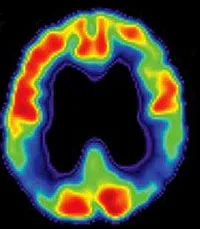

7) cuál de estas opciones describe mejor a esta imagen?

A) Una resonancia magnética de una demencia fronto-temporal

B) Un PET de una hidrocefalia

C) Una tomografía computada de un derrame cerebral en el lóbulo occipital

D) Una tomografía computada de una demencia fronto-temporal